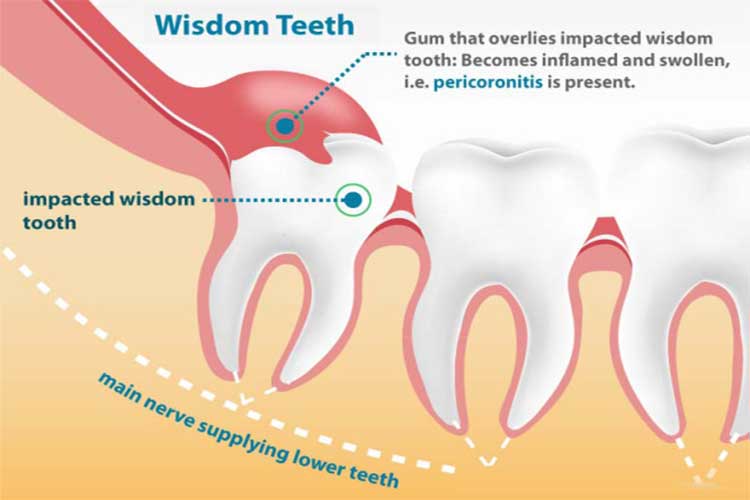

Your wisdom teeth might be impacted or even infected, which makes them hard to clean and maintain good oral hygiene. This is why it’s important to have them removed before they become a problem.

Crowding is a common cause of the need for dental extraction. Most people simply do not have the space in their mouths to allow wisdom teeth to fit properly. Extraction of wisdom teeth is very common. In fact, some people have such limited space that premolars need to be taken out to allow for proper alignment of all of their teeth. This is usually done just before braces are placed by their orthodontist.

Deep decay allows bacteria to enter and kill the pulp of the tooth. This results in an abscessed or infected tooth. Many times this can be treated with root canal therapy. If there is not enough tooth structure to allow restoration, the tooth will need to be extracted.

Periodontal disease causes loosening of the teeth due to bone loss. When this has continued untreated for many years, it will cause the teeth to need to be extracted. This happens most rapidly in people with diabetes.